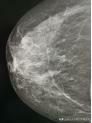

01X線

X線攝影的原理是基於人體組織之間有密度和厚度的差別,當 X 線透過人體不同組織結構時,被吸收的程度不同,所以到達螢屏或膠片上的 X 線量即有差異,形成明暗或黑白對比不同的影像。